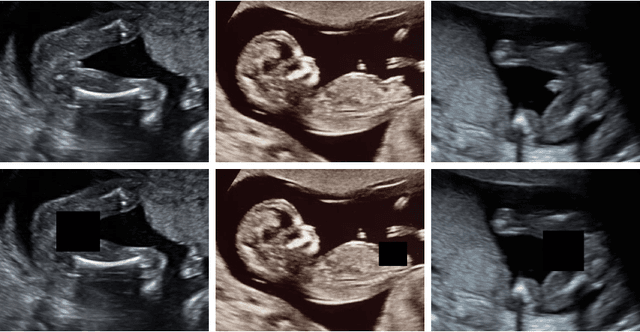

Abstract:Ultrasound (US) imaging is highly effective with regards to both cost and versatility in real-time diagnosis; however, determination of fetal gender by US scan in the early stages of pregnancy is also a cause of sex-selective abortion. This work proposes a deep learning object detection approach to accurately mask fetal gender in US images in order to increase the accessibility of the technology. We demonstrate how the YOLOv5L architecture exhibits superior performance relative to other object detection models on this task. Our model achieves 45.8% AP[0.5:0.95], 92% F1-score and 0.006 False Positive Per Image rate on our test set. Furthermore, we introduce a bounding box delay rule based on frame-to-frame structural similarity to reduce the false negative rate by 85%, further improving masking reliability.